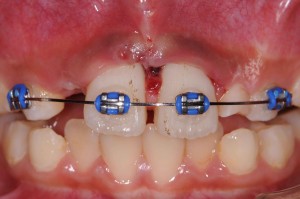

右上中切歯(右の真ん中の歯)は歯根破折、左上中切歯は歯牙脱臼を起こしていました。脱臼については、そこそこ固定できればどのような方法でもくっついてくれますが、歯根破折の場合は、処置によって大きく結果が異なります。

ポイントは「元あった位置にいかにピッタリ戻し、その位置で強固に固定できるか」ということです。この症例では、横の乳歯が一方はない、もう一方がぐらぐらしているということで固定源としては使えませんので、一つ飛ばして真ん中から3番目の乳歯にそれを求めなければなりません。

さらに固定した位置がずれないように、また、割れている部位に介在している一日経って弾力が出てしまった血餅をつぶしながらの固定ですから、大きな硬いワイヤーを曲げて使用しなければ目的を達することができない難しさもあります(血餅の排除に限度があったため、僅かな隙間は存在します)。

さらに固定した位置がずれないように、また、割れている部位に介在している一日経って弾力が出てしまった血餅をつぶしながらの固定ですから、大きな硬いワイヤーを曲げて使用しなければ目的を達することができない難しさもあります(血餅の排除に限度があったため、僅かな隙間は存在します)。